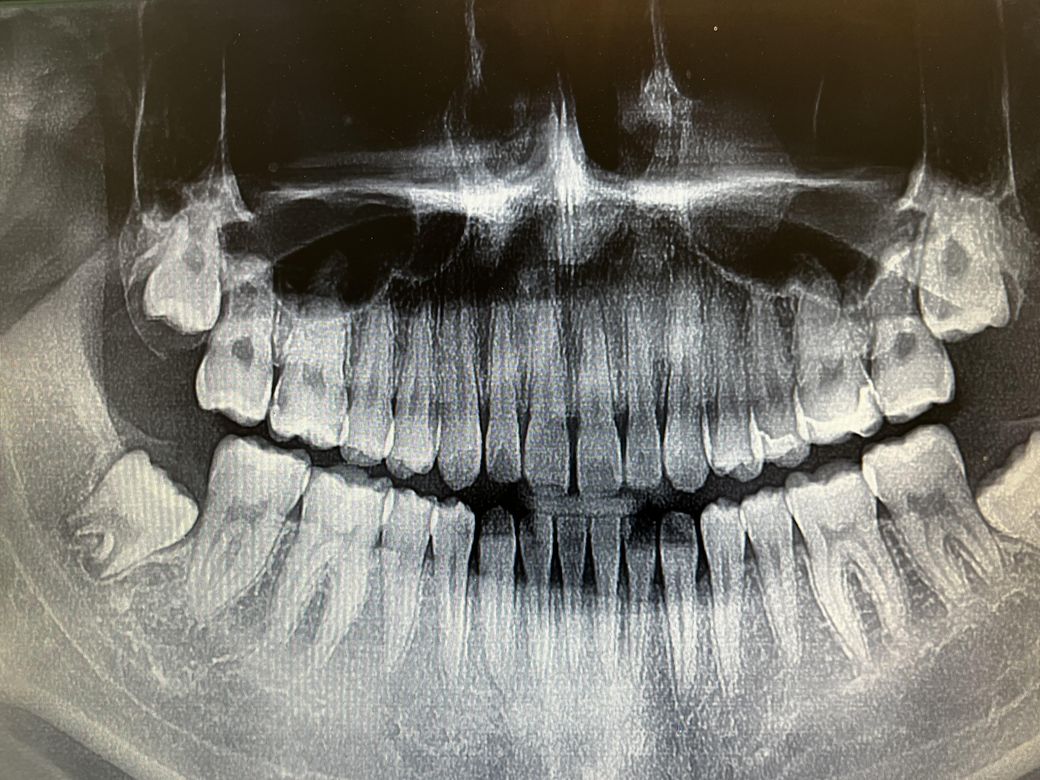

치실을 하다가 위아래로 빼는데 한달도 안된게 들뜰수있나요? 통증이나 시림은 없는데 부은것같거나 뭐가 낀것처럼 느껴져요 아래사진은 저번주 토요일 사진입니다 오른쪽 위 2개를 인레이 한부분이고요 혀로 만져보면 잘 붙어있는것같아요 그리고 현재 크라운 임시치아 사용중인데 다음에 가서 붙힐때 임시재료 땔때 아픈가요?

• 1번 째 사진